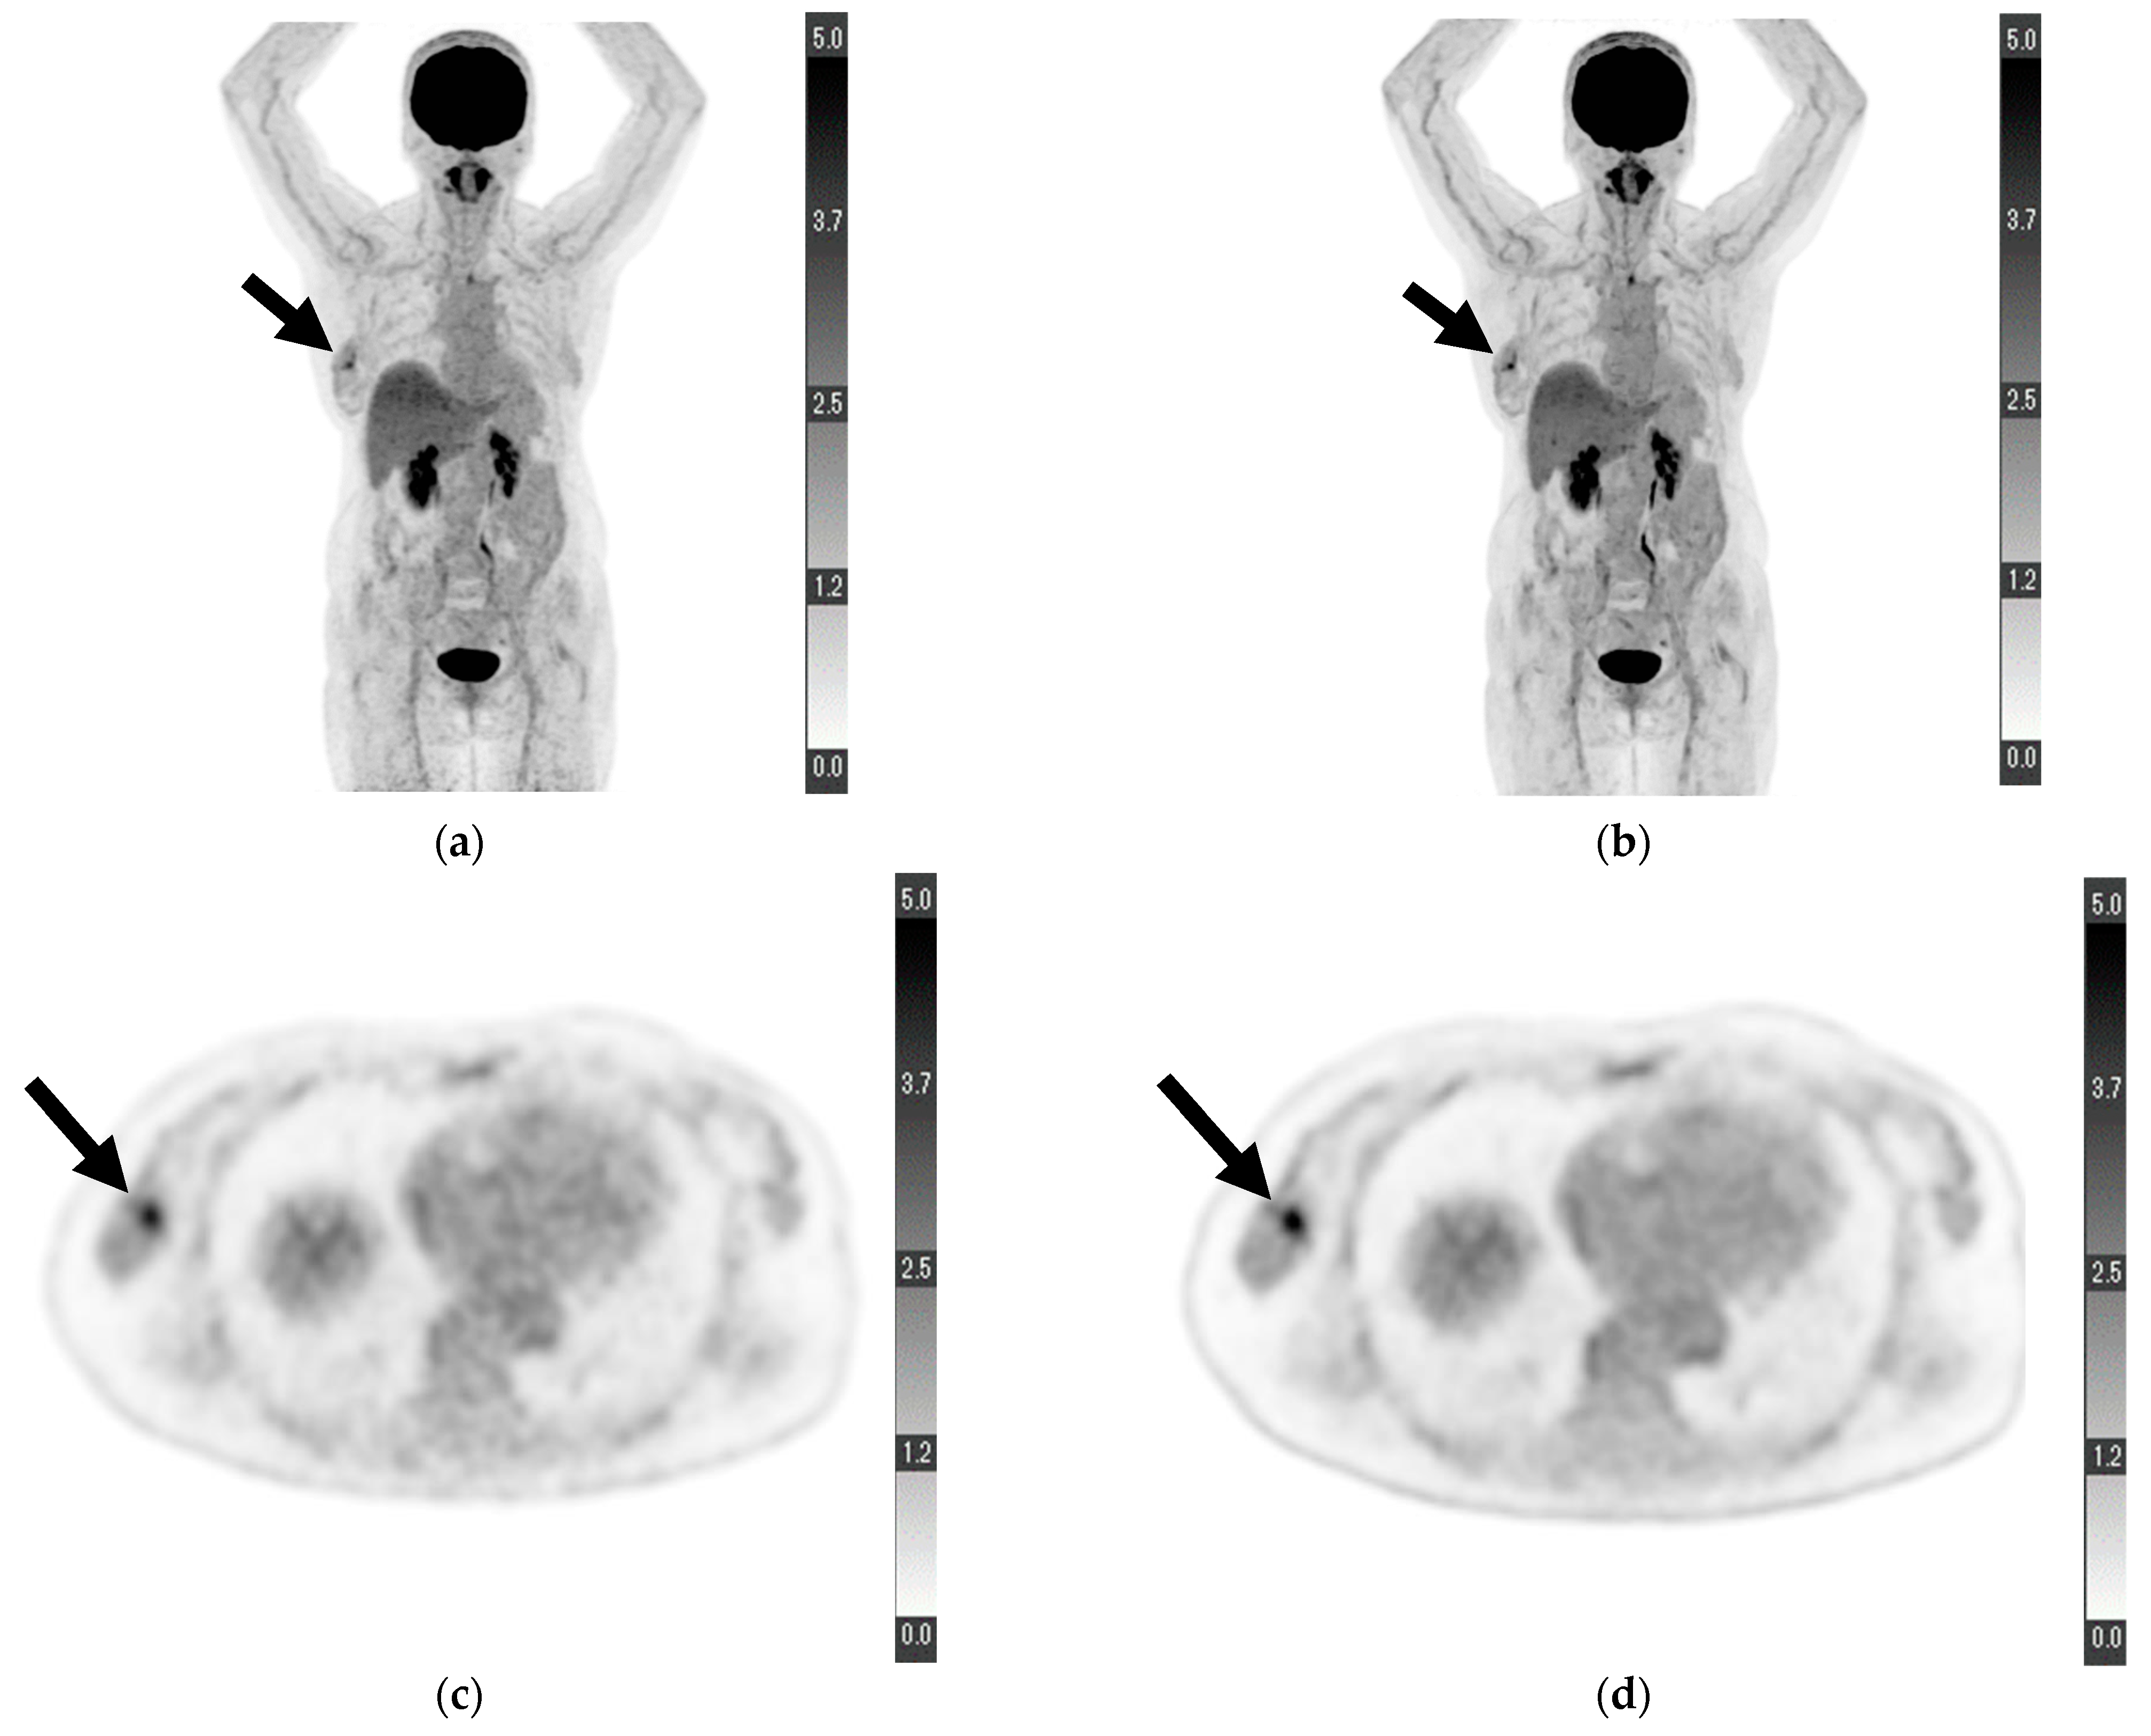

For “depiction of primary lesion”, the average score provided by reader 1 was higher for DL-PET than for cPET; however, no significant difference was observed (4.673 ± 0.695 vs. 4.455 ± 0.857, p = 0.121). Conversely, the score provided by reader 2 for DL-PET was significantly higher than that for cPET (4.364 ± 0.969 vs. 4.000 ± 1.089, p = 0.049). The scores of readers 1 and 2 for DL-PET were significantly higher than those for cPET in terms of “noise” (reader 1, 4.782 ± 0.498 vs. 4.073 ± 0.663, p < 0.001; reader 2, 4.491 ± 0.573 vs. 3.855 ± 0.621, p < 0.001), “clarity of mammary gland” (reader 1, 4.309 ± 0.836 vs. 3.909 ± 0.727, p = 0.003; reader 2, 4.109 ± 0.737 vs. 3.291 ± 0.737, p < 0.001), and “overall image quality” (reader 1, 4.636 ± 0.557 vs. 4.073 ± 0.663, p < 0.001; reader 2, 4.473 ± 0.539 vs. 3.904 ± 0.470, p < 0.001). The relevant data are shown in Table 2. Figure 1 shows a sample PET from a patient with some visual analysis scores higher in DL-PET than in cPET.

Figure 1.

Maximum-intensity projection of (a) conventional positron emission tomography (PET) reconstruction and (b) deep learning (DL) PET restoration of a woman in her 60 s with invasive ductal carcinoma in the right breast (arrows): invasive diameter, 15 mm; nuclear grade, 2; lymphatic invasion, negative; vascular invasion, negative; estrogen receptor, positive; progesterone receptor, positive; HER2 receptor, positive; Ki-67 staining, 25.5%; and nodal stage, 0. Axial view of a tumor cross-section for the same woman using (c) cPET reconstruction and (d) DL-PET restoration. Images were scored on a five-point scale from 1 = extremely poor to 5 = excellent. The scores of reader 1 for “depiction of the primary lesion”, “noise”, “clarity of mammary gland”, and “overall image quality” were 4, 5, 5, and 5 for cPET and 5, 5, 5, and 5 for DL-PET, respectively; the scores of reader 2 were 3, 4, 4, and 4 for cPET and 5, 5, 5, and 5 for DL-PET, respectively.